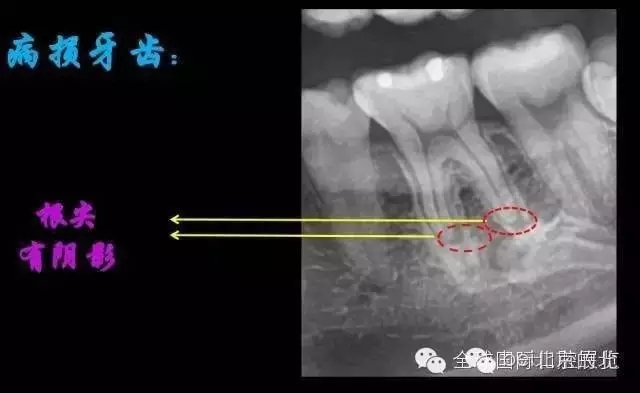

我們?cè)賮?lái)看看患牙:

X-RAY示:近遠(yuǎn)中牙根都有陰影存在,牙周膜都有些許增寬,近中頸部位置牙體有低密度減低影,就是楔狀缺損的位置。

病因分析:楔狀缺損的深齲致牙髓壞死引起的根尖炎癥,應(yīng)囑患者以后改變刷牙方式

診斷:36慢性根尖炎急性發(fā)作